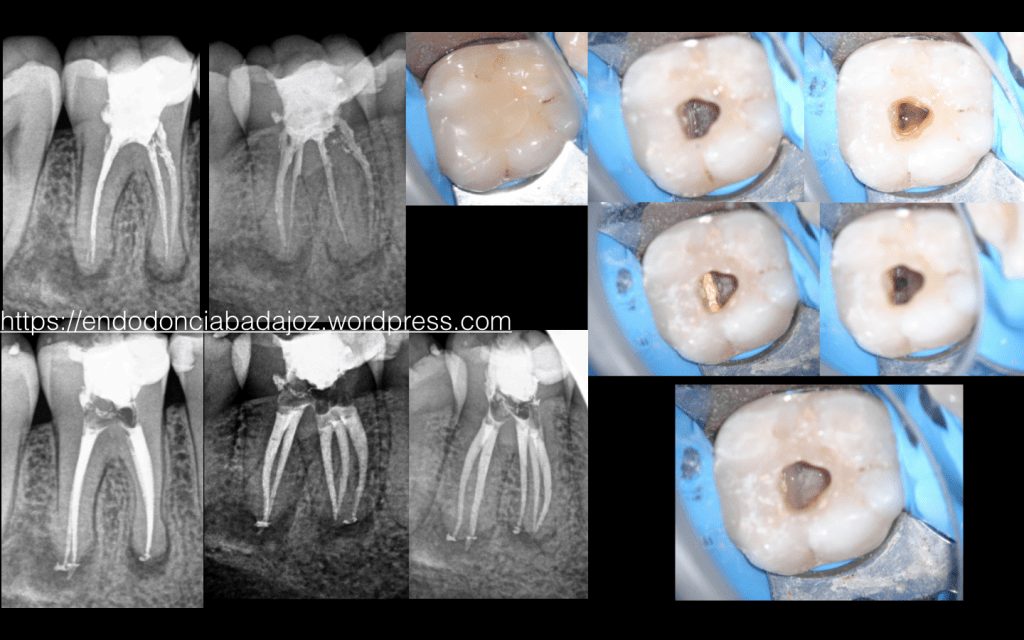

Molares inferiores…. pero qué bonitos son!!!!

Estimados colegas, para empezar, un saludo. Llevo ya casi 11 años en el fantástico mundo de la endodoncia y en todo este tiempo he visto los fracasos que existen en los molares inferiores, míos propios y de compañeros, una de las piezas que más fracasan. Esto ha hecho que tenga especial cuidado en esta pieza. Esta entrada es porque creo que subestimamos la anatomía dental interna, ¿por qué no nos esforzamos un poco , aquellos que realizamos este tratamiento, en aprenderla?, Nos ayudaría enormemente a ser más predecible. Existe un gran articulo de mi amigo Oliver Valencia :

que nos va a ayuda en la disposición de esta anatomía. Es más fácil buscar y tratar algo que sospechamos que puede existir que algo que ni siquiera lo sabemos.

Para ello, subo unos casitos, que espero sean de interés.